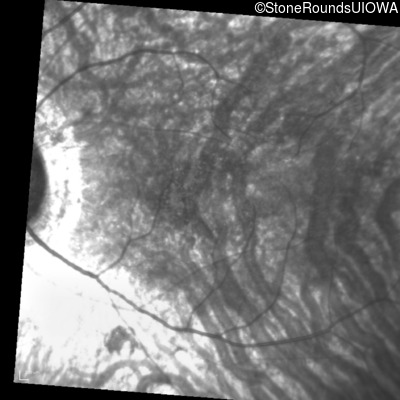

Infrared Fundus Photograph - Right - 20/125 sc

Exemplar